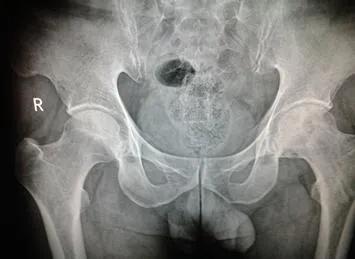

这时拍X光片会看到股骨头内有半月状软骨下断裂,股骨头软骨下骨小梁与软骨分离,股骨头骨皮质断裂、软度蹋陷。